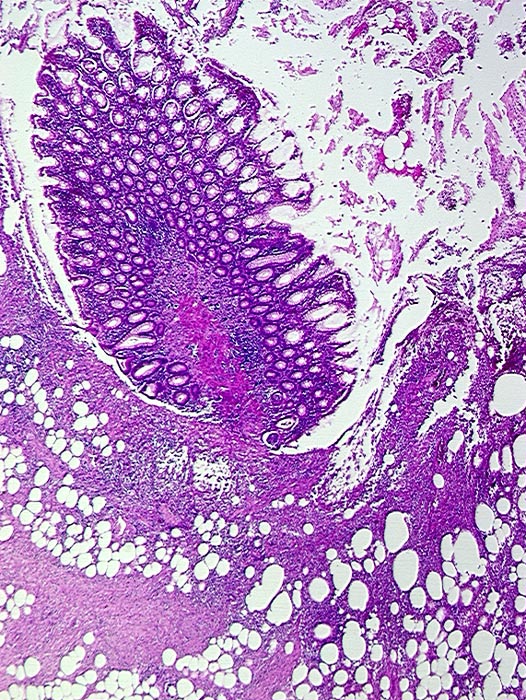

AP/ Divertikulitis

Divertikulitis

Darm, Anus

Kolon Sigma

Morphologie

-

Pathologischer Befund

Normalbefund